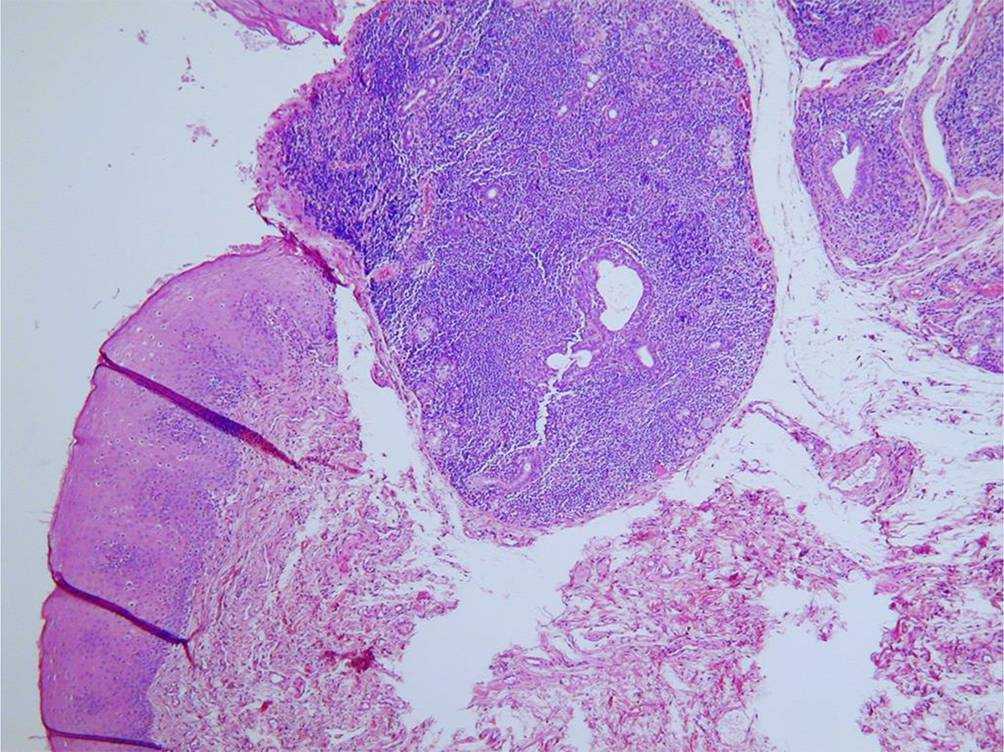

Bei Patienten mit Hinweisen auf ein Sjögren-Syndrom ist zur Diagnosesicherung, zur Abgrenzung anderer mit einer Sicca-Symptomatik einhergehenden Erkrankungen wie einer Sarkoidose oder einer IgG4-assoziierten Erkrankung sowie zur Abgrenzung eines sekundären Sjögren-Syndroms eine Speicheldrüsenbiopsie erforderlich [21, 35]. Die Biopsie erfolgt als ambulanter Eingriff an der Unterlippe und die histologische Auswertung von lymphozytären Aggregaten durch die Bestimmung des Fokus-Scores nach Chisholm und Mason ([5]; Abb. 3). Ein Fokus-Score von ≥1 weist mit einer Spezifität von 82 % auf ein Sjögren-Syndrom hin [41].

Abb. 3

Typisches histologisches Bild eines Sjögren-Syndroms mit fokaler lymphoplasmazellulärer Infiltration (zur Verfügung gestellt von OA Dr. M. Scarpatetti, Institut für Pathologie, Medizinische Universität Graz)